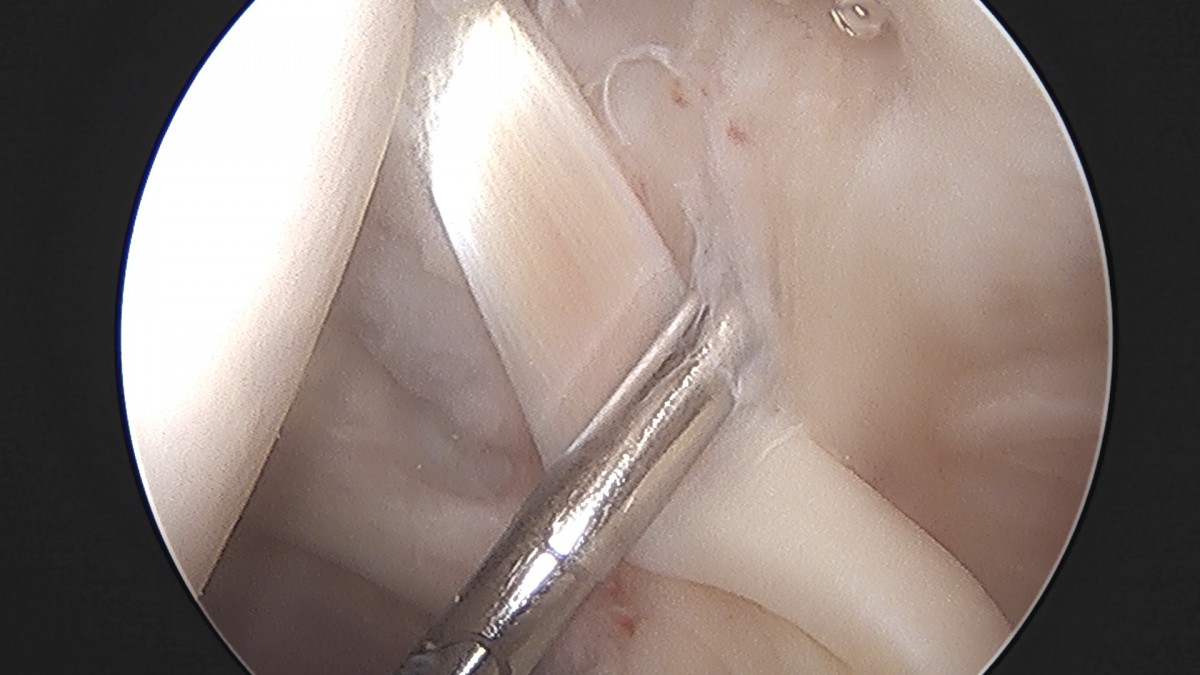

이재상원장님 어깨 석회 제거술 송현O 환자

작성자 최고관리자 댓글 0건 조회 800회 작성일 25-09-16 15:39